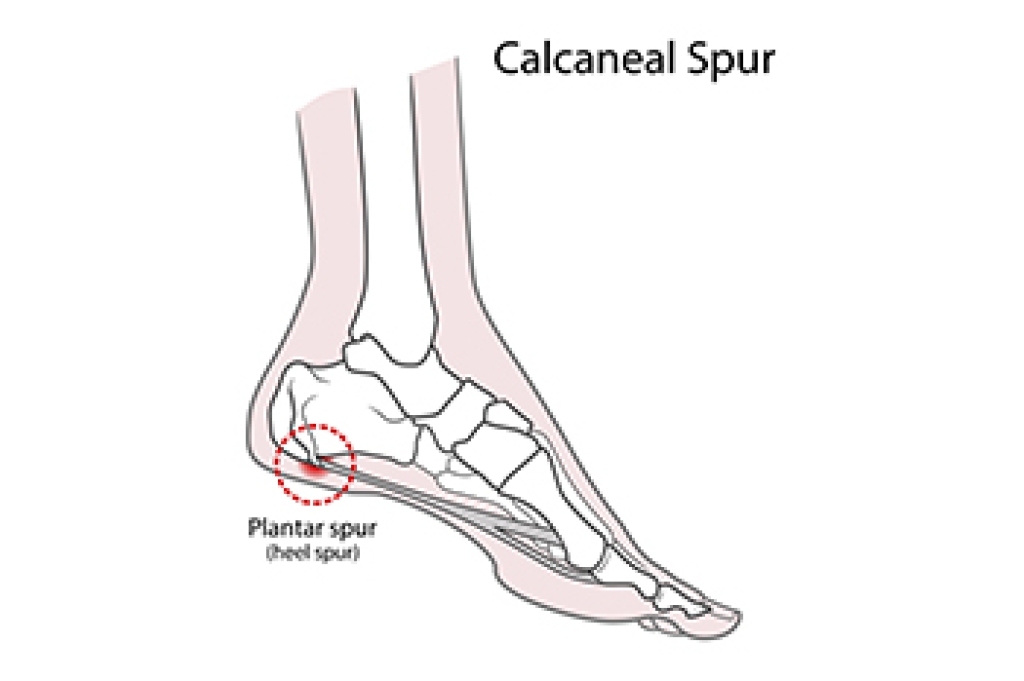

Heel spurs, bony outgrowths at the bottom of the heel bone, can be a source of persistent foot discomfort. Formed due to calcium deposits, heel spurs often accompany conditions like plantar fasciitis. The pain associated with heel spurs typically arises during weight-bearing activities, especially after rest periods. While rest and proper footwear are important components of managing heel spurs, specific exercises can provide relief. Stretching exercises, such as calf stretches and towel curls, may help to alleviate tension in the Achilles tendon and plantar fascia. Rolling a frozen water bottle under the foot can reduce inflammation. Strengthening exercises, like toe-tapping and marble pickups, enhance foot and ankle muscles, promoting better support. A podiatrist treats heel spurs. If you have developed this condition, it is suggested that you visit this type of doctor who can help you with appropriate treatment and guide you toward additional stretches.

Heel spurs are formed by calcium deposits on the back of the foot where the heel is. This can also be caused by small fragments of bone breaking off one section of the foot, attaching onto the back of the foot. Heel spurs can also be bone growth on the back of the foot and may grow in the direction of the arch of the foot.

Older individuals usually suffer from heel spurs and pain sometimes intensifies with age. One of the main condition's spurs are related to is plantar fasciitis.

Pain

The pain associated with spurs is often because of weight placed on the feet. When someone is walking, their entire weight is concentrated on the feet. Bone spurs then have the tendency to affect other bones and tissues around the foot. As the pain continues, the feet will become tender and sensitive over time.

Treatments

There are many ways to treat heel spurs. If one is suffering from heel spurs in conjunction with pain, there are several methods for healing. Medication, surgery, and herbal care are some options.